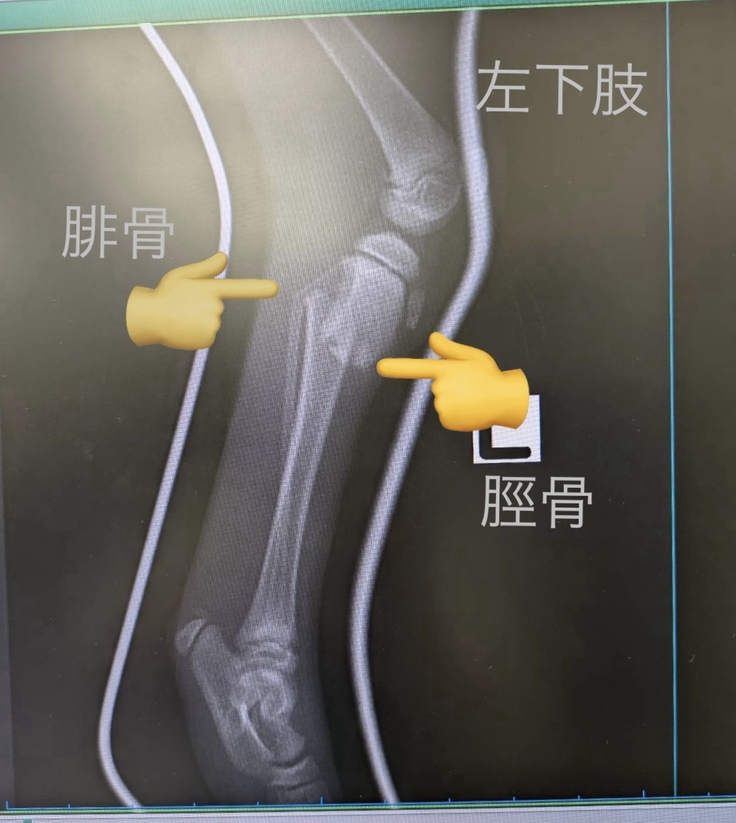

翌日、総合動物病院へ行き精査してもらうと左足に関しては脛骨も腓骨も折れていることが分かりました。そこで他の保護猫で手術歴のある動物病院へ緊急に受診し、同日入院となりました。

左下肢は脛骨骨折と腓骨の不完全骨折で脛骨は上腕と同じくプレートでの固定をしました。腓骨は細いため自然に癒合するのを待つことになりました。